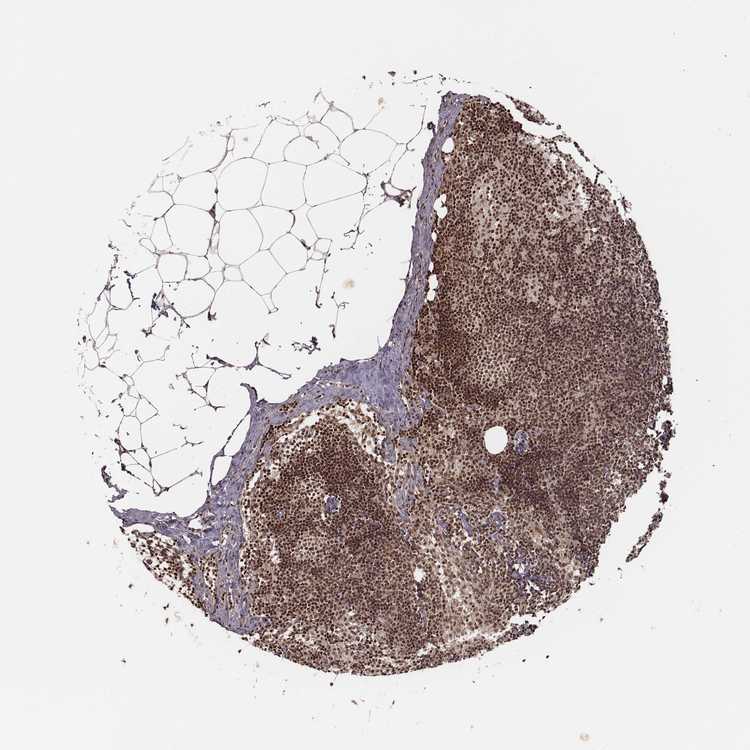

TISSUE PRIMARY DATA LYMPH NODE Show tissue menu

Lymph node

LYMPH NODE - Antibody stainingi

Antibody staining in the annotated cell types in the current human tissue is reported as not detected, low, medium, or high, based on conventional immunohistochemistry profiling in selected tissues. This score is based on the combination of the staining intensity and fraction of stained cells.

Each image is clickable and will lead to virtual microscopy that enables deeper exploration of all samples and also displays staining intensity scores, fraction scores and subcellular localization as well as patient and tissue information for each sample.

Antibody HPA073519

Germinal center cells High

Non-germinal center cells High